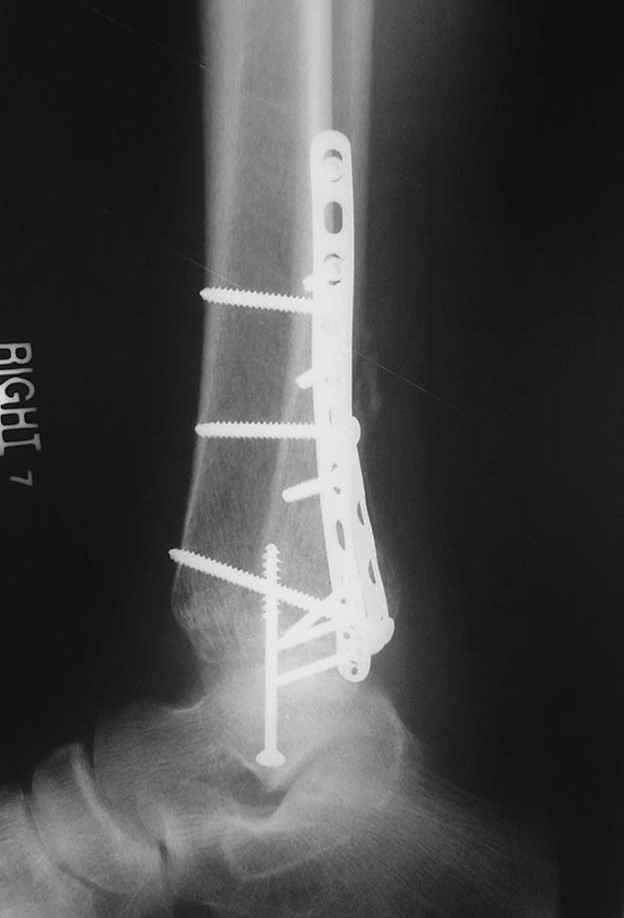

Re: ANKLE FRACTURE

Второй случай сделан из одного разреза